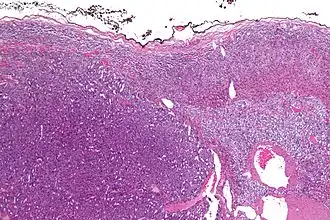

![]() Micrografía de un carcinoma adrenocortical (a la izquierda de la imagen, azul oscuro) y de la corteza adrenal de la que surgió (arriba a la derecha de la imagen, rosa / azul claro). La médula suprarrenal benigna está presente (mitad derecha de la imagen, gris/azul). Tinción H&E. | ||

Los tumores suprarrenales a menudo no se biopsian antes de la cirugía, por lo que el diagnóstico se confirma al examinar la muestra quirúrgica por un patólogo. En general, los carcinomas adrenocorticales a menudo son grandes, con una superficie de corte de color canela y áreas de hemorragia y necrosis. En el examen microscópico, el tumor generalmente muestra láminas de células atípicas con cierta semejanza con las células de la corteza suprarrenal normal. La presencia de invasión y actividad mitótica ayuda a diferenciar cánceres pequeños de adenomas adrenocorticales. Hay varias variantes relativamente raras de carcinoma corticoadrenal: